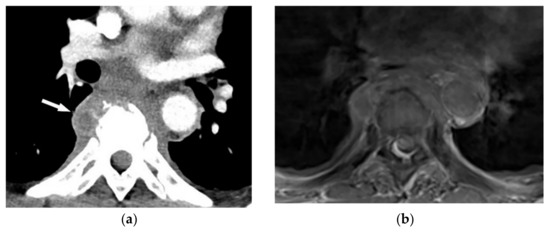

8.1. Pyogenic Spondylodiskitis

Pyogenic spondylodiskitis presents with loss of vertebral end plate definition and marrow edema. It displays hypointensity on T1-weighted images and hyperintensity on T2-weighted and STIR images. Various types of disk post-contrast enhancement (e.g., homogenous, patchy, and peripheral) may be detected [39]. Abscess or phlegmons demonstrate heterogeneous mixed signal intensity on both T1-weighted and T2-weighted images, with probable spinal cord compression. Rim-like or diffuse post-contrast enhancement are usually seen within these soft tissues. Diffusion weighted imaging (DWI) is valuable for differentiating the abscess from other paravertebral lesions (Figure 12) [39,41].

Figure 12.

A 71-year-old man with back pain and fever. The contrast-enhanced CT in axial plane (a) demonstrates para-spinal soft tissue mass (arrow) with adjacent vertebral body cortical destruction. Axial pre-contrast (b) and post-contrast T1WFS (c) images at the level of T6-T7 show hypo to isointense paravertebral soft tissue mass with peripheral rim enhancement (arrow) after injection of gadolinium suggestive for paravertebral abscess formation. Sagittal STIR (d) image shows adjacent subchondral bone marrow edema as hypersignal intensity. Posterior elements are spared with normal signal intensity. Aspiration was performed and culture was compatible for brucellosis.